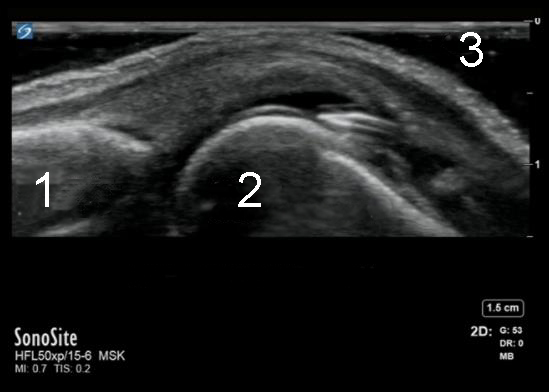

手部 MCP 关节注射图像

近端趾骨

远端掌骨头

凝胶